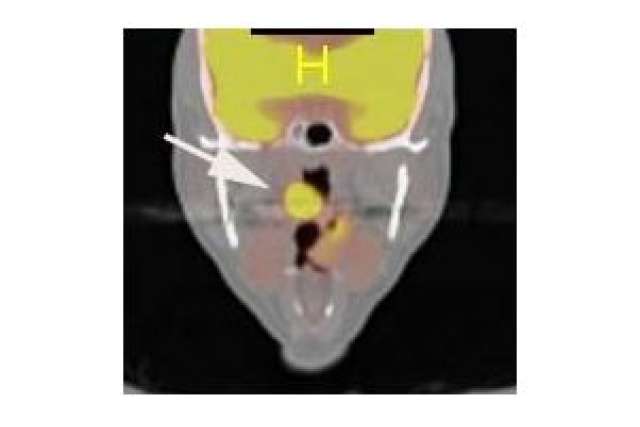

Led by Dr. Eri Srivatsan and Dr. Marilene Wang, UCLA Jonsson Comprehensive Cancer Center members and co-authors of the study, researchers found the link between the protein gigaxonin and head and neck cancer while investigating the chemotherapy drug cisplatin. The drug is successfully able to kill cancer cells by interacting with the protein p16 which is commonly produced in HPV-positive cancers.

“We studied the interaction of p16 in the nucleus of the cancer cell after treatment with cisplatin, and observed how the protein interacted with gigaxonin,” said Wang, professor-in-residence of head and neck surgery. “We found the combination of the proteins stops the cell cycle, allowing chemotherapy treatment to prevent the cell from growing and killing the cancer cell.”

For the study, Wang, Srivatsan and eight colleagues at UCLA also analyzed 103 archival clinical samples from head and neck cancer patients to identify the relationship between p16 nuclear expression and cancer-free survival. They found that patients with cancers with p16 expression had better survival rates than without p16 expression.